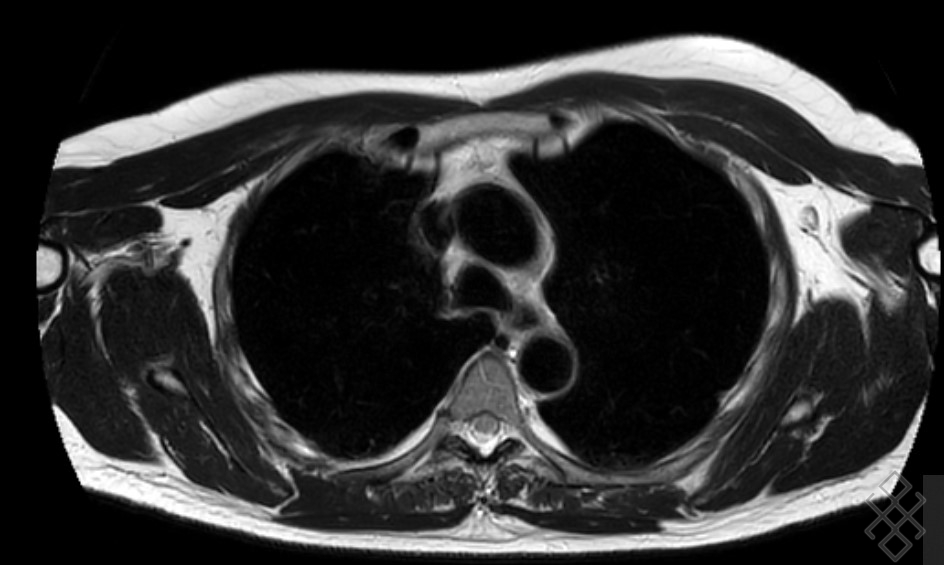

l’IRM du thorax est limité et ne permet pas

d’explorer fiable le parenchyme pulmonaire en

routine clinique. Ses indications sont en bien

établies dans la pathologie pleurale, médiastinale

et vasculaire thoracique. La contraste

l’IRM se mis à profit pour caractérisation

tissulaire des tumorales, et pour l’étude de

l’envahissement de la paroi thoracique et des

organes de voisinage . Les technique radiologique

fiable de IRM souvent utilise1 pour explorer le

madiastin son : Les coupes à ponderation sur T1 , T1

Fatsat , T1 FS Gadolinium , T2 , T2 FS ...

Image radiologique IRM normale

du thorax et de mediastin en coupe axiale pondere

sur T2 |